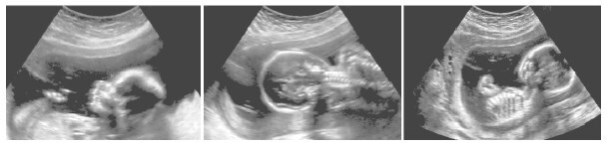

Ультразвуковое сканирование растущего плода позволяет врачам следить за развитием ребенка.